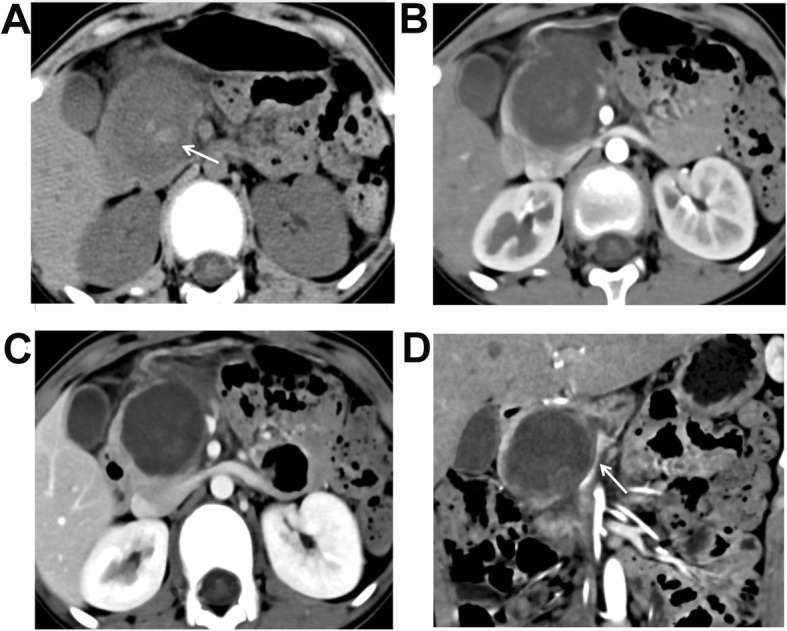

Fig. 4.

A 12-year-old female patient with vomiting and upper abdominal pain. Plain CT scanning + enhanced scanning showed pseudo-papillary neoplasm of pancreas (SPNP). a Plain scanning showed a huge oval cystic mass at the pancreatic head, and the boundaries were clear. Small patchy bleeding focuses were found in the mass (white arrow). b Low enhancement of the lesion was found in the arterial phase, which was lower than the normal pancreas. c A little enhancement of the cystic components was found in the portal venous phase, which showed “floating cloud” sign. d Reconstructed coronal image showed compressing and circuity of the superior mesenteric vein (white arrow)